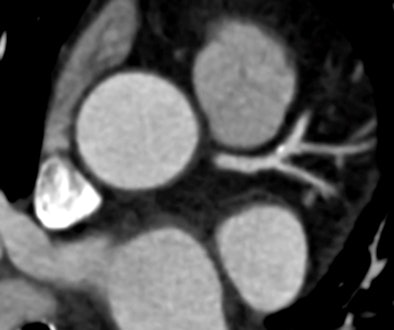

![]() |

| Compared to filtered back projection reconstructions in CCTA of obese patients, subjective image quality was improved with use of the iTRIM algorithm. |

Schoepf and colleagues applied the iTRIM algorithm to a group of obese patients -- all had a body mass index (BMI) greater than 30 -- and compared the image quality of traditional FBP reconstruction at 250 msec temporal resolution with the iTRIM technique "where precious seconds were shaved off the temporal resolution to 200 msec," he said.

Results were as follows:

- There were no significant differences in attenuation between FBP- and TRIM-reconstructed series.

- There were no differences in contrast-to-noise ratio between FBP- and TRIM-reconstructed series.

- TRIM-reconstructed data showed significantly lower motion artifact severity scores than FBP (2.0 versus 2.5; p < 0.05).